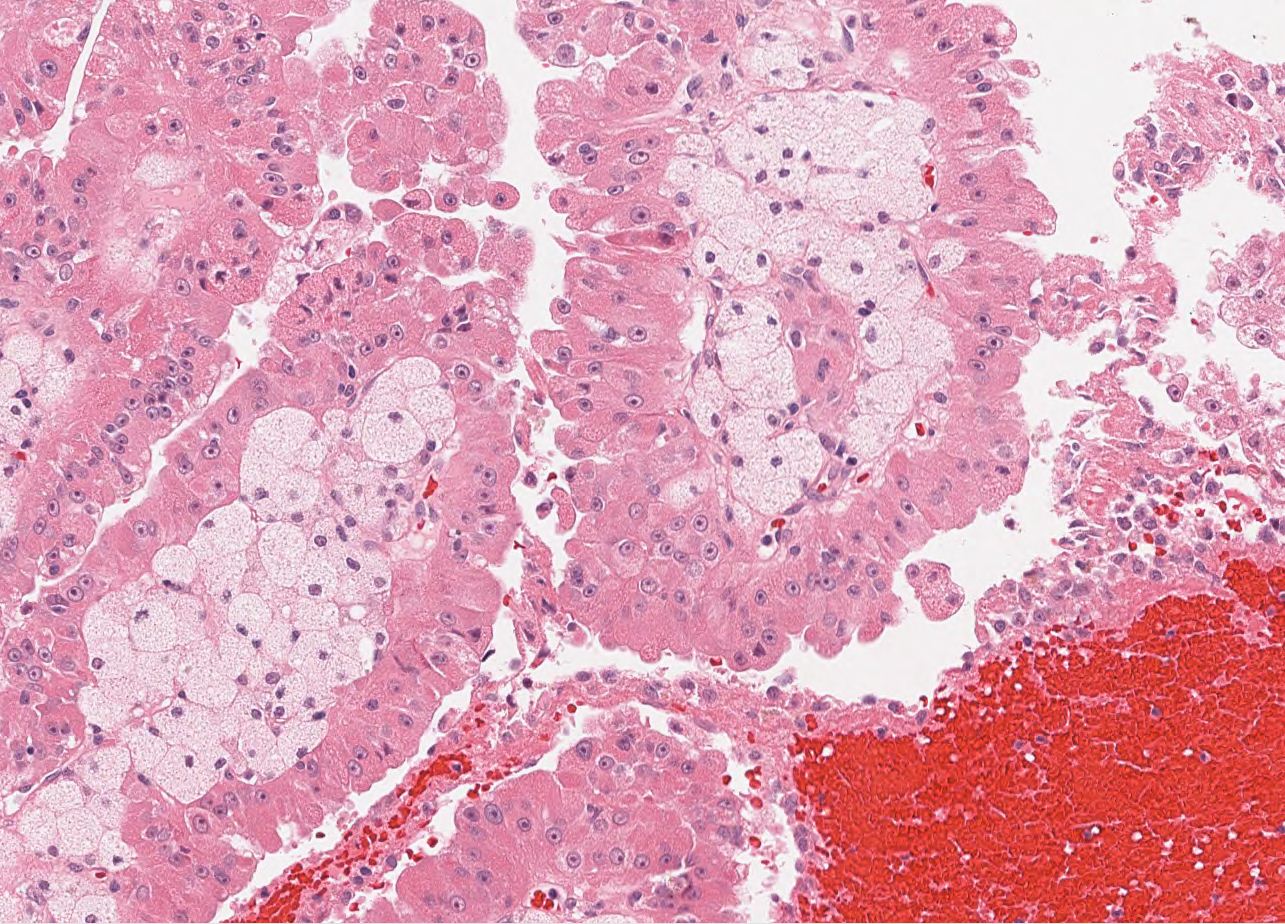

Renal tumor grading

Case ID: 564